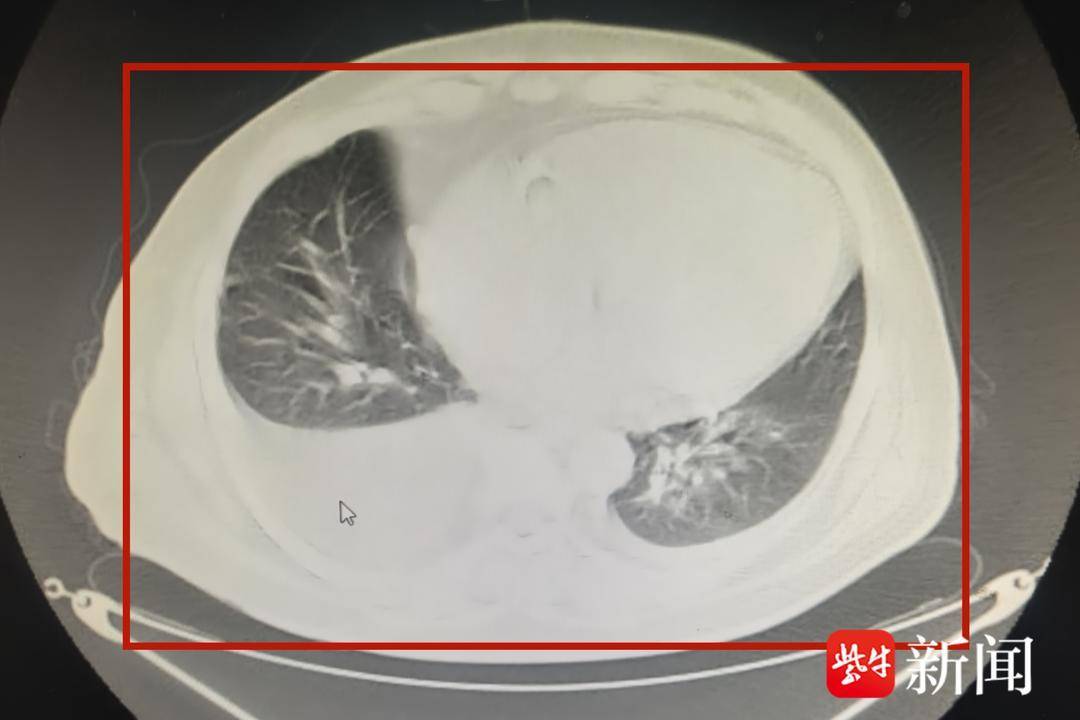

转入肾病科住院时,老董严重气喘、无法行走,由家人用轮椅推入。肾病科副主任中医师胡娟娟检查后发现,患者N端脑利钠肽高达3万多pg/mL,是正常值的120多倍,提示急性心衰。胸部ct和彩超检查显示,患者的胸腔、腹腔积液,连心脏也被“水”淹没了。

影像检查显示,老董的心脏差点被积液“淹没”